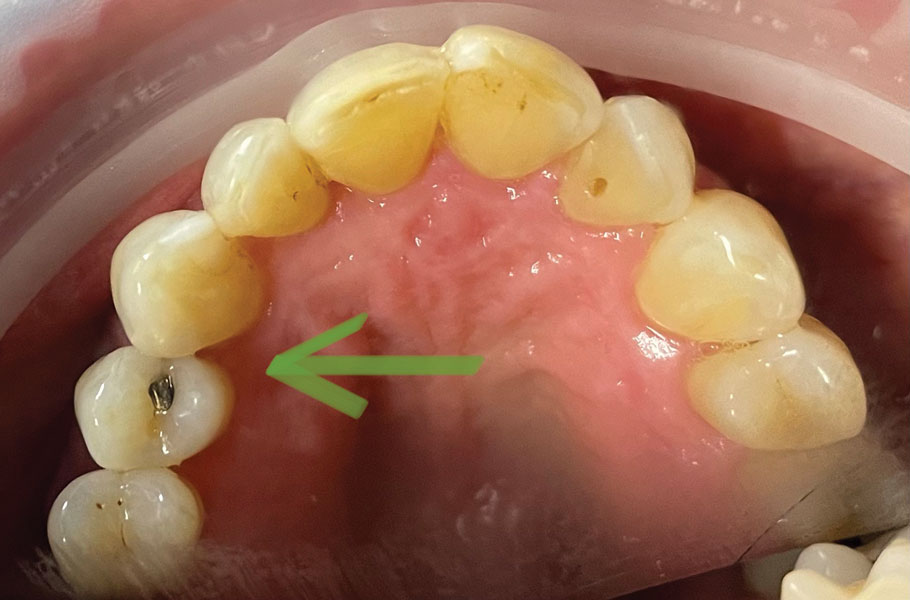

OPERATIVE DENTISTRY Class III anterior direct composite restoration